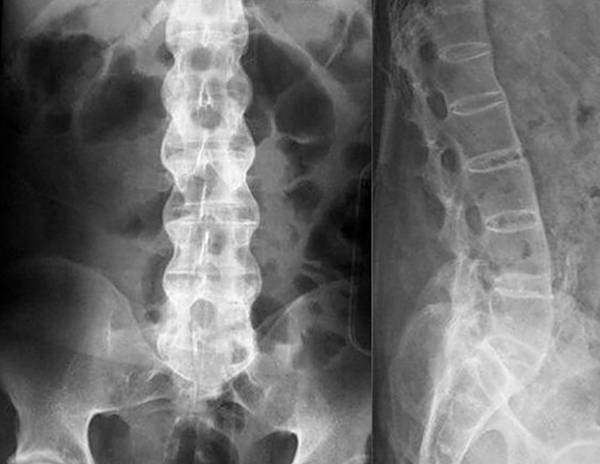

Если симптомы явно указывают на грыжу, остеохондроз или радикулит, для диагностики обычно применяют рентгенологическое исследование. Рентгенография относится к самым простым и доступным способам, к тому же, для снимка требуется совсем немного времени, в отличие от КТ, где пациент должен сохранять неподвижность достаточно долго. Для оценки состояния сосудов и мягких тканей назначают УЗИ, а при подозрении на инфекционную природу недуга обязательно проводятся лабораторные исследования крови и мочи. По полученным результатам врач подбирает больному оптимальный способ лечения.

При заболеваниях позвоночника чаще всего для диагностики применяют рентгенографию

- рентген – смотрят наличие грыжи, трещины в позвоночнике;